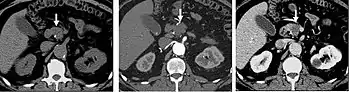

Detection and characterization of renal parenchymal masses is a frequent indication for CT. An initial noncontrast CT is important for detecting calcium or fat in a lesion, and to provide baseline attenuation of any renal masses. Following noncontrast scanning, intravenous contrast is injected and a corticomedullary phase is obtained at approximately 70 seconds (figure 7a, 7b). The corticomedullary phase is characterized by enhancement of the renal cortex as well as the renal vasculature. This phase is valuable in the evaluation of benign renal variants, lymphadenopathy and vasculature, however certain medullary renal masses may not be visible during this phase due to minimal enhancement of the medulla and collecting system. The parenchymal phase is obtained approximately 100–200 seconds after the injection of contrast material (figure 7c). Parenchymal phase imaging demonstrates continued enhancement of the cortex, enhancement of the medulla, and various levels of contrast material in the collecting system. The parenchymal phase is highly important for the detection and characterization of renal masses, parenchymal abnormalities, and the renal collecting system. This method of imaging does not evaluate for abnormalities of the collecting system.

Common renal masses can occasionally be differentiated from each other using this imaging technique. Renal cell carcinomas and oncocytomas typically demonstrate intense heterogeneous enhancement on the parenchymal phase images and cannot be reliably differentiated from each other but can be distinguished from other renal masses. Angiomyolipomas (AML’s) also demonstrate intense contrast enhancement but characteristically contain macroscopic fat which can be detected on the noncontrast images, and can help to differentiate AML’s from renal cell carcinomas and oncocytomas. Renal lymphoma on the other hand, will often have decreased enhancement when compared to the renal parenchyma on the parenchymal phase images.

FIGURE 7. Selected images from a renal mass specific protocol CT. Corticomedullary phase (axial 7a) demonstrates peripheral enhancement of the renal cortex with minimal opacification of the renal medulla. There is a large renal cell carcinoma in the left kidney (right in image) which can be differentiated from the normal renal parenchyma by the heterogeneous and differential enhancement. The renal artery and vein are opacified in this phase as well. The collecting system is not opacified (coronal reformat 7b). In the parenchymal phase, the renal cortex and the medulla are enhancing. The renal cell carcinoma in the left kidney is not as well defined when compared to the corticomedullary phase images, but is actually slightly more conspicuous. There is some contrast noted within the collecting system during this phase (7c).